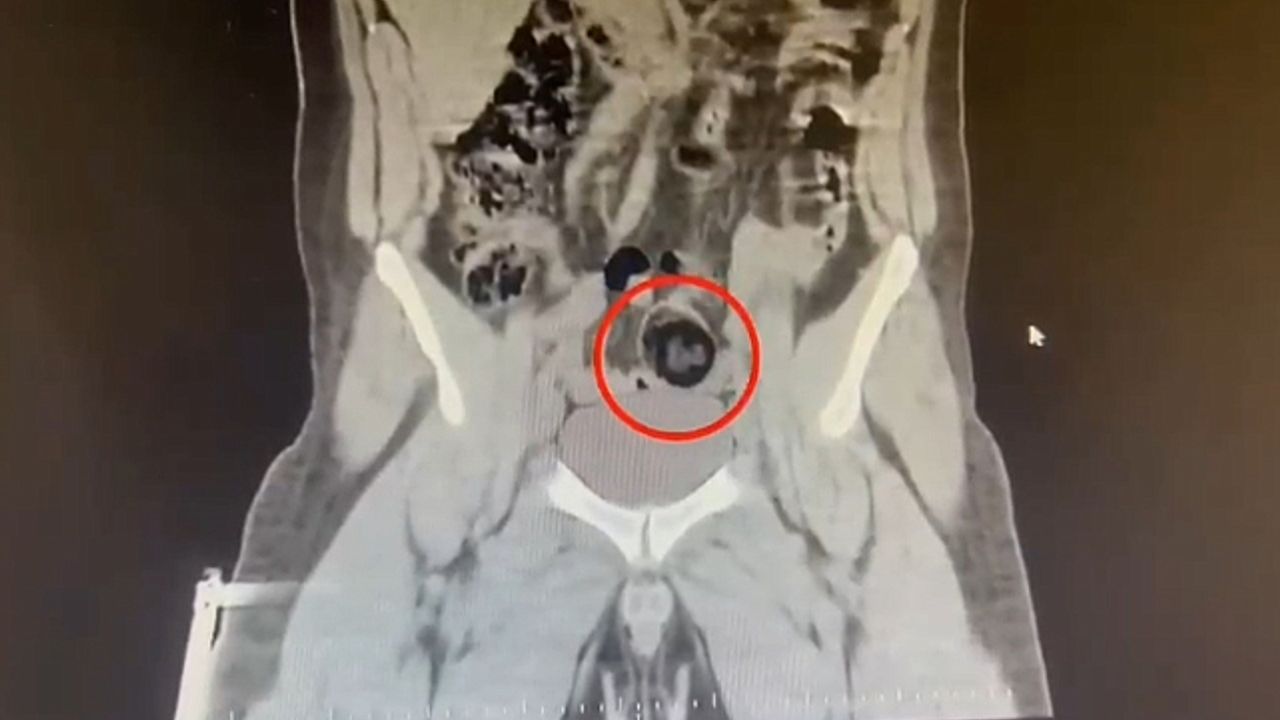

Kars Emniyet Müdürlüğü Narkotik Suçlarla Mücadele Şube Müdürlüğünce, savcılık koordinesinde kent merkezinde uluslararası uyuşturucu madde ticareti yapan kurye şahıslara yönelik operasyon düzenlendi. Bu kapsamda narkotik ekiplerince durdurulan yolcu otobüsünde İranlı kurye yakalanarak gözaltına alındı. Şüpheli hareketler sergilen kurye götürüldüğü hastanede yapılan iç beden muayenesinde makatında cisim olduğu anlaşıldı. Kuryenin makatındaki 105,98 gram metamfetamin gerçekleştirilen cerrahi müdahaleyle çıkarıldı. Gözaltına alınarak emniyete getirilen kurye, çıkarıldığı mahkemece "TCK-188 uyuşturucu veya uyarıcı madde imal ve ticareti yapmak" suçundan tutuklanarak cezaevine gönderildi.